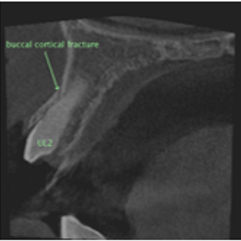

CBCT Imaging & Diagnostics

We are qualified to prescribe and review 3D CBCT imaging. This provides precise 3D views of root of teeth for accurate diagnosis and planning—minimising guesswork and improving outcomes.

- High-resolution 3D visualisation

- Targeted field of view to reduce exposure

- Improved detection of complex anatomy